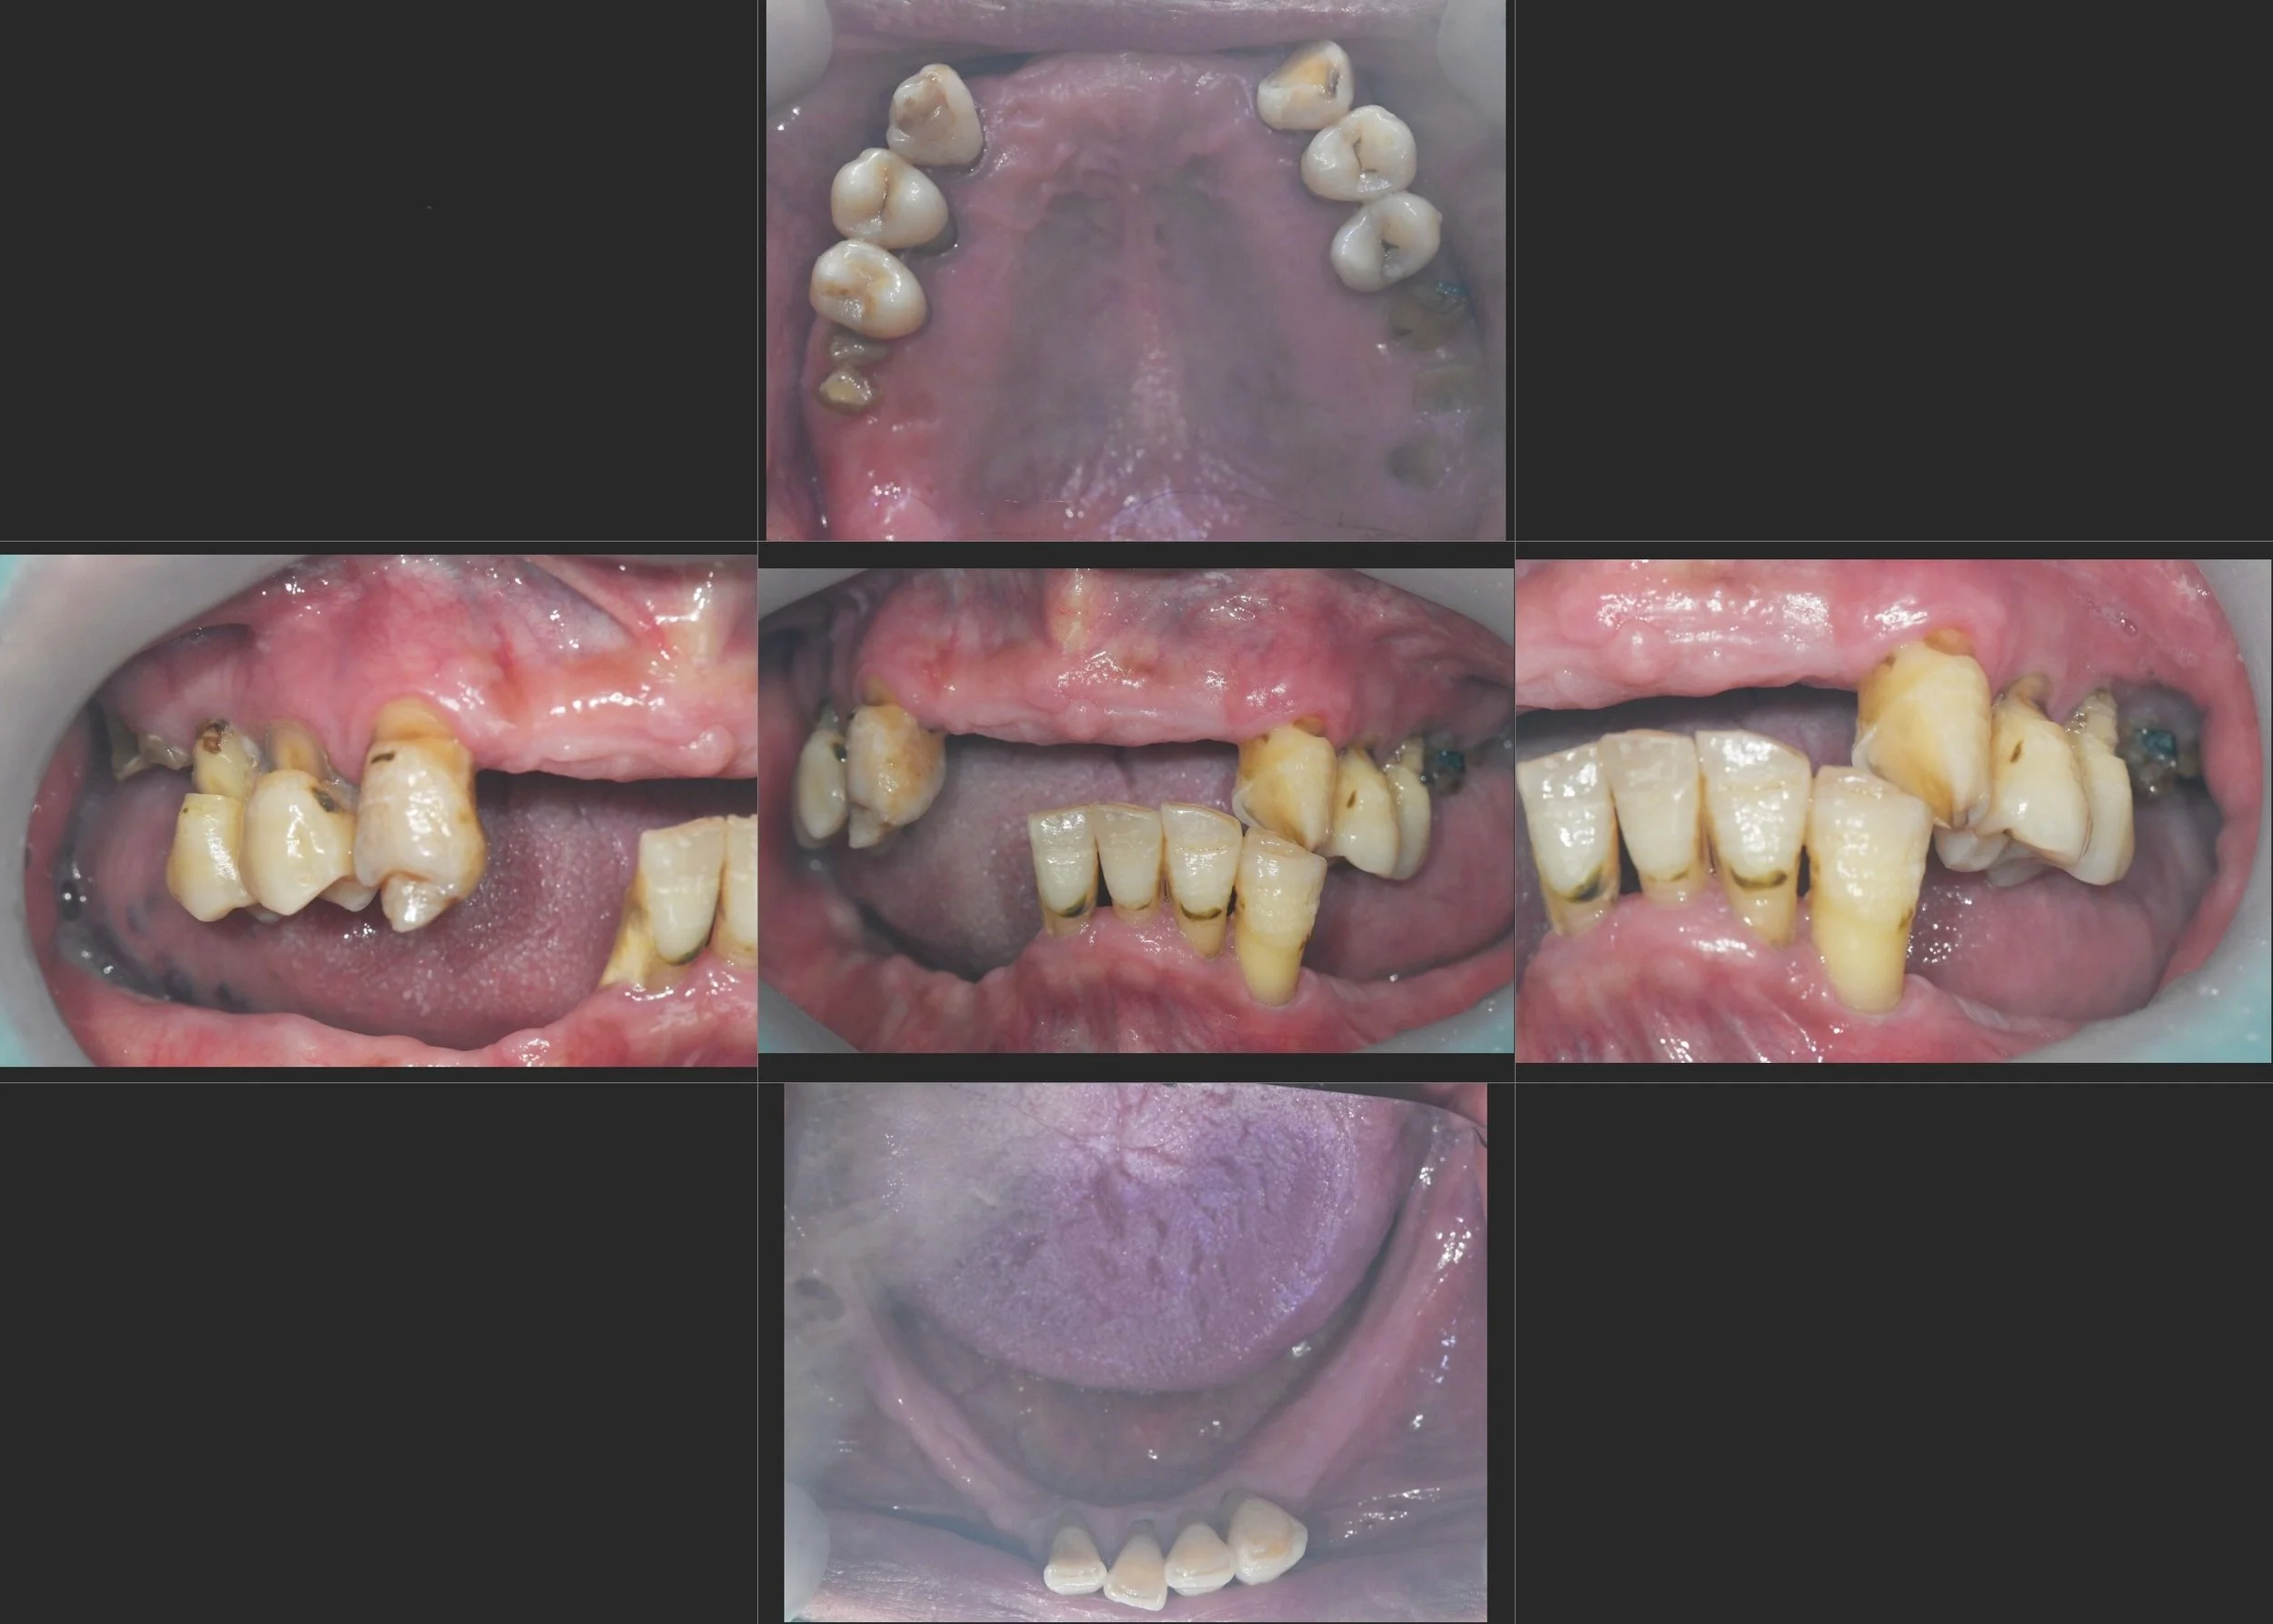

INTRA ORAL - BEFORE